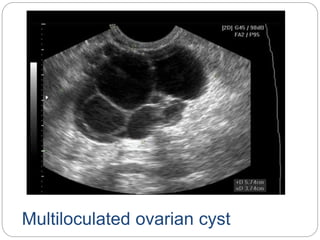

Multiloculated ovarian cyst

Ovarian Cyst  Cystsare fluid filled spaces within the ovary.  very common and could be physiological / pathological, benign/ malignant  Functional or physiological cysts are either follicular or of corpus luteum origin.  Follicular cysts form when a follicle fails to rupture at midcycle leading to its continuous enlargement. Usually these cysts are asymptomatic and disappear without any intervention within one or two months  Similarly a persistent corpus luteum might fail to disintegrate before menstruation and enlarge in size

 Both follicularand luteal cysts could become haemorrhagic if bleeding occured within them leading to rapid increase in size and severe pain.  they might cause severe pain only if they are large in size (>7 cm) and cause pressure symptoms or torsion of the whole ovary compromising blood flow when surgical intervention is indicated